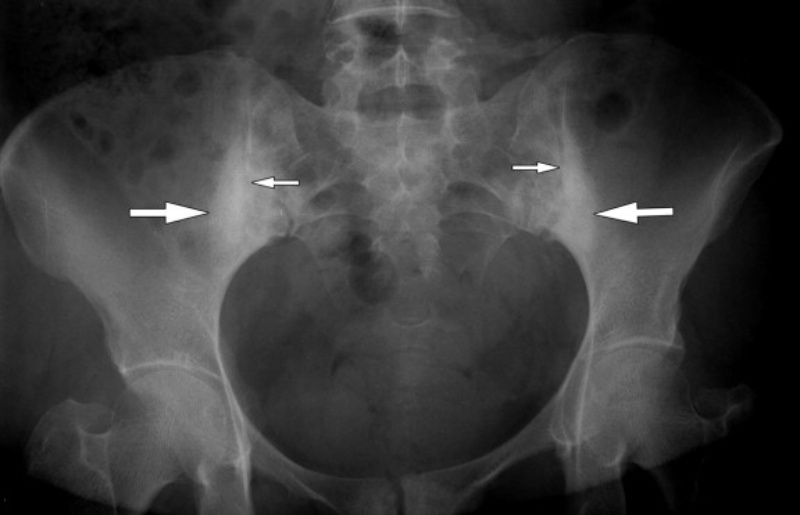

Viêm khớp cùng chậu thường khó chẩn đoán vì dễ bị nhầm lẫn với các tình trạng khác gây đau lưng dưới. Bác sĩ có thể chỉ định chụp X Quang, chụp cắt lớp (CT) hoặc chụp cộng hưởng từ (MRI) để chẩn đoán tình trạng này.

Tia X là một dạng bức xạ điện từ, giúp tạo ra hình ảnh về cấu trúc bên trong cơ thể. Loại tia này được phát hiện lần đầu vào năm 1895 và tia X chụp được hình ảnh mô người lần đầu tiên vào năm 1896 (2). Chụp X Quang là phương pháp chẩn đoán hình ảnh sử dụng phổ biến nhất. Bác sĩ có thể sử dụng X Quang để chẩn đoán các tình trạng liên quan đến xương chậu như:

Chụp X Quang vùng chậu là một phương pháp chẩn đoán đơn giản và không đau. Phụ nữ mang thai cần thông báo cho bác sĩ, vì thai nhi có thể bị phơi nhiễm với bức xạ từ tia X.